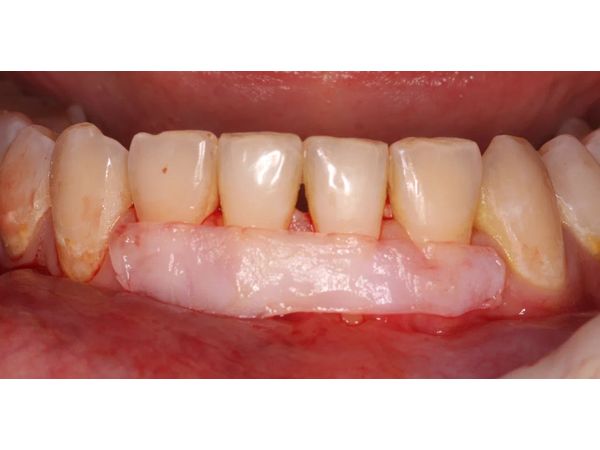

- Извлекли свободный десневой трансплантат (СДТ) с нёба и сняли с него слой эпителия, чтобы создать раневую поверхность. Именно такой трансплантат выбрали из-за тонкой десны, возможно, она истончилось, так как с неё брали ткани для предыдущих операций.

- Ввели трансплантат в тоннель и стабилизировали швами, которые прижимают и вытягивают лоскуты вдоль оси зубов.